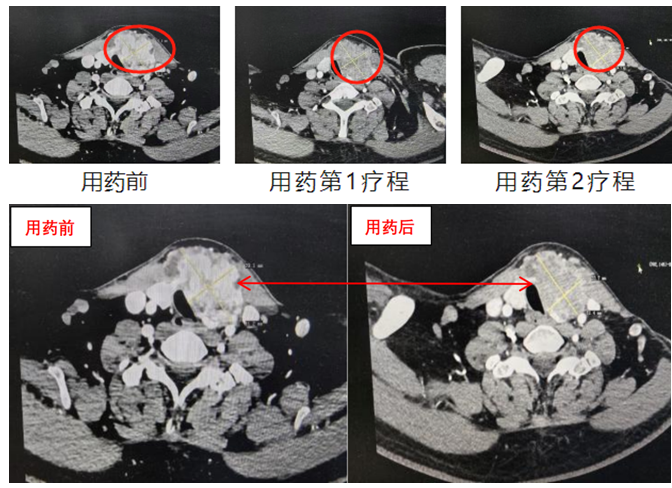

CT檢查發現,他頸部左側有一個巨大甲狀腺腫瘤,直徑達到了6cm,幾乎有鴨蛋大小,而且腫瘤侵犯了頸部肌肉,氣管,食管和頸部大血管。

于是抱著一絲希望,他來到北大深圳醫院乳腺甲狀腺外科。接診的李朋副主任醫師發現鴨蛋大的腫瘤把氣管壓迫成了一個窄縫,侵犯了頸部肌肉、氣管、食管和頸內靜脈,同時可見頸部淋巴結多發轉移,初步診斷為“局部晚期甲狀腺癌”。

幸運的是,馬強在接受3個月多納非尼治療后,奇跡逐漸顯現,腫瘤負荷的血液指標下降明顯。復查頸部CT顯示,腫瘤從一個“鴨蛋”縮小成一個“雞蛋”,最長徑較前縮小1.5cm,短徑較前縮小0.5cm,氣管壓迫減輕,頸部多發淋巴結轉移也較前縮小。

“腫瘤縮小后,氣管和腫瘤之間就有間隙,手術完整切除腫瘤的成功概率就有了。”李朋說。尤其是CT顯示腫瘤內部密度和血供明顯減低,這說明腫瘤活性在下降,為后續手術創造了條件。